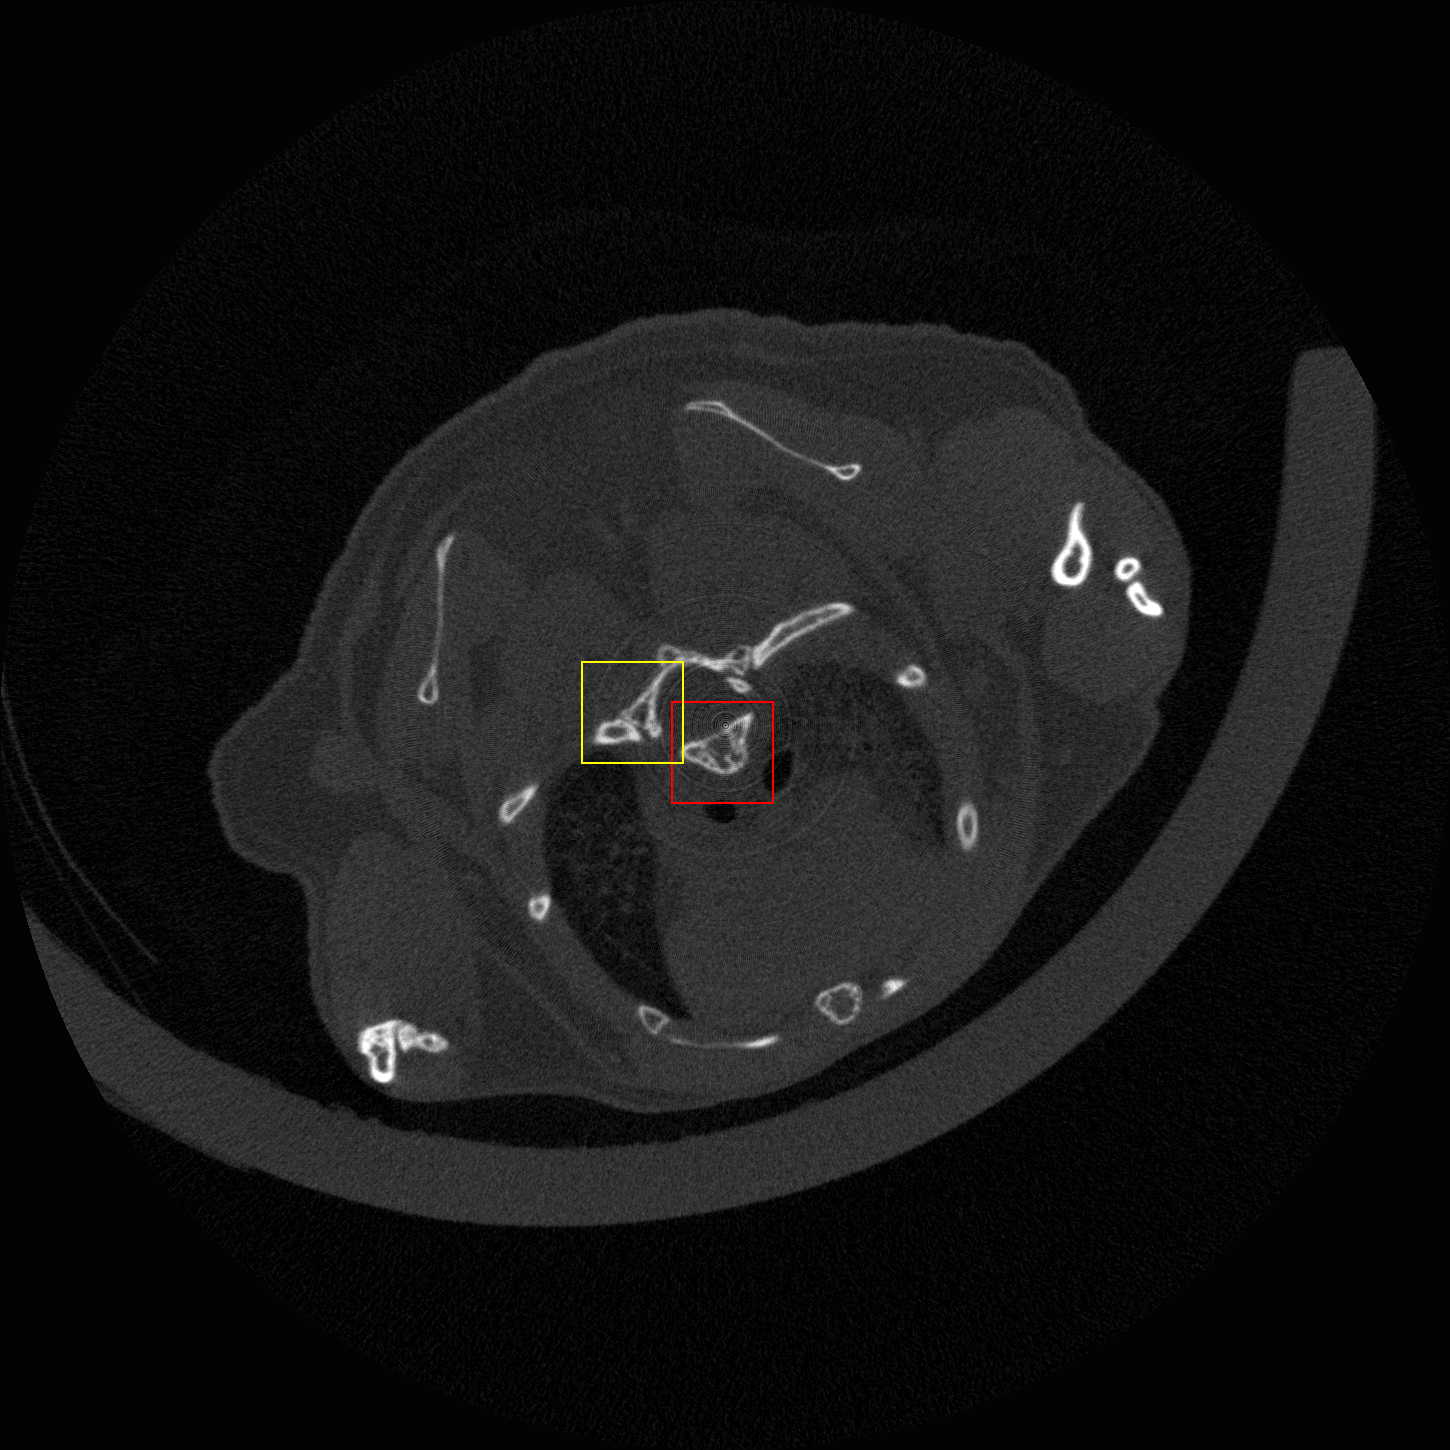

Figure 6: Visual comparison of SRCT Case 222 from the abdominal dataset. The display window is [-160, 240] HU. The restored anatomical features are shown in the red and yellow boxes. (Zoomed for visual clarity).

III-E Experimental Results on the Abdominal Dataset

We further compared the above-mentioned algorithms on the abdominal benchmark dataset. A similar trend can be observed on this dataset. Our proposed GAN-CIRCLE can preserve better anatomical informations and more clearly visualize the portal vein as shown in Fig. 6. These results demonstrate that PSNR-oriented methods (FSRCNN, ESPCN, LapSRN) can significantly suppress the noise and artifacts. However, it suffers from low image quality as judged by the human observer since it assumes that the impact of noise is independent of local image features, while the sensitivity of the Human Visual System (HVS) to noise depends on local contrast, intensity and structural variations. Fig. 6 displays the LRCT images processed by GAN-based methods (SRGAN, G-Adv, GAN-CIRCLE, GAN-CIRCLEs, and GAN-CIRCLEu) with improved structural identification. It can also observed that the GAN-based models also introduce strong noise into results. For example, there exist tiny artifacts on the results of GAN-CIRCLEu. As the SR results shown in Fig. 6, our proposed approaches (GAN-CIRCLE, GAN-CIRCLEs) are capable of retaining high-frequency details to reconstruct more realistic images with relatively lower noise compared with the other GAN-based methods (G-Adv, SRGAN). Table II show that G-Fwd achieves the best performance in PSNR. Our proposed methods GAN-CIRCLE and GAN-CIRCLEs both obtain the pleasing results in terms of SSIM and IFC. In other words, the results show that the proposed GAN-CIRCLE and GAN-CIRCLEs generate more visually pleasant results with sharper edges on the abdominal dataset than the competing state-of-the-art methods.